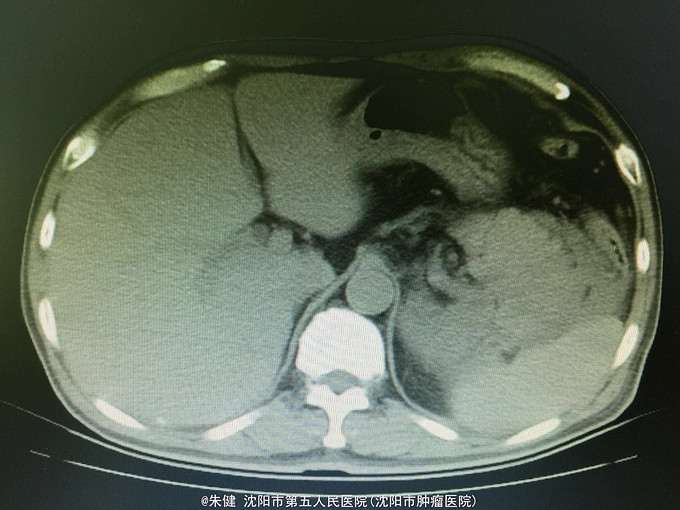

男,52岁 主诉:上腹部胀痛30小时, 现病史:30小时前饮酒后引起上腹部胀痛,持续性,逐渐加重,累及腰背部,恶心,呕吐数次胃内食物,无发热,未治疗,因不见好转来诊;病来无心悸、气短,排气、排便可,排尿正常。

一般状态可,腹部平坦,未见肠形及蠕动波,剑突下及左侧上腹部压痛,轻度肌紧张,未及包块,无移动性浊音,肠音正常,肾区无扣痛。 辅助检查:血常规:白细胞13.6*10^9/L,中性83.3/L;尿淀粉酶:214U/L,上腹部CT:左侧胸腔积液,左肺下叶可见斑片及索条状影;胆囊增大,胆道内未及结石影;胰腺形态及密度正常,胰腺尾部周围可见索条状影及积液影。

诊断:急性胰腺炎 处理:给予禁食、补液、抗炎及抑肽酶治疗,病情逐渐好转,一周后出院。